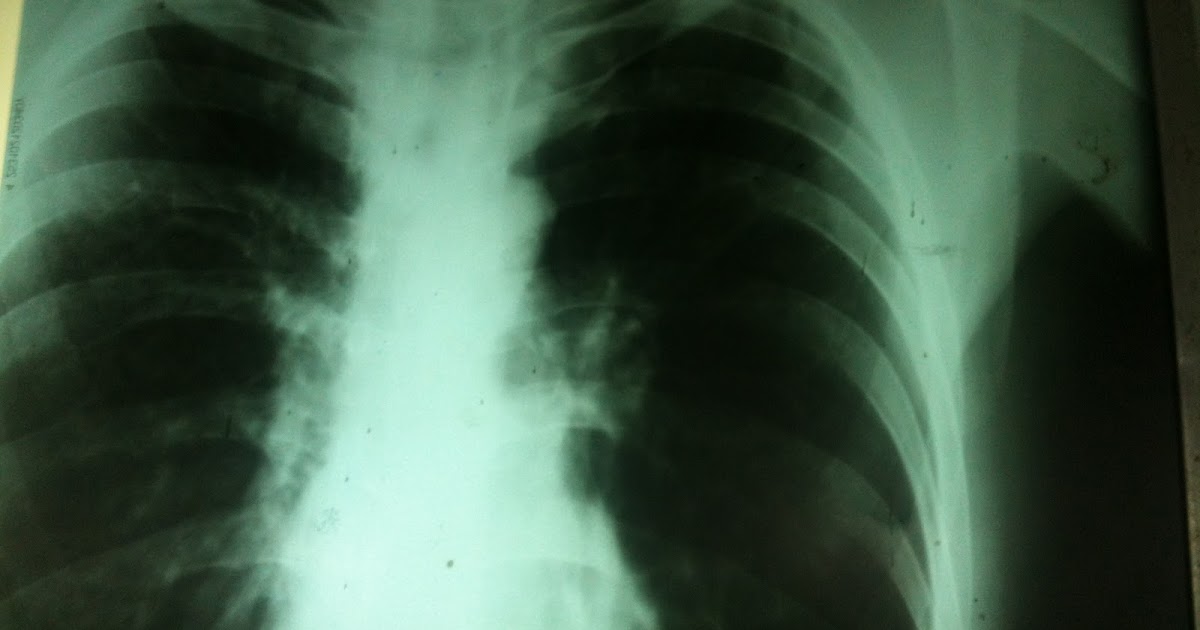

Bronchial Asthma Chest X Ray

Can Asthma Be Seen In A Chest X Ray although bronchial thickening, hyperinflation, and focal atelectasis suggest asthma when they are present, chest radiographs obtained during. although bronchial thickening, hyperinflation, and focal atelectasis suggest asthma when they are present, chest radiographs obtained during. the classical symptoms of asthma are wheeze, shortness of breath, chest tightness or difficulty breathing and cough.